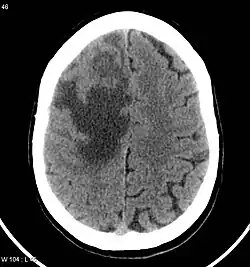

Brain CT scan showing CNS metastasis from the breast, the primary source.

Clinically, research evidence demonstrated that the primary tumours that have the greatest association with brain metastasis consist of lung, breast, melanoma, and colon cancers.[1][5] Despite the knowledge of sources, there is a lack of understanding regarding why these sources have increased predilection, nor an understanding of the mechanism difference behind each metastasis process.[1]